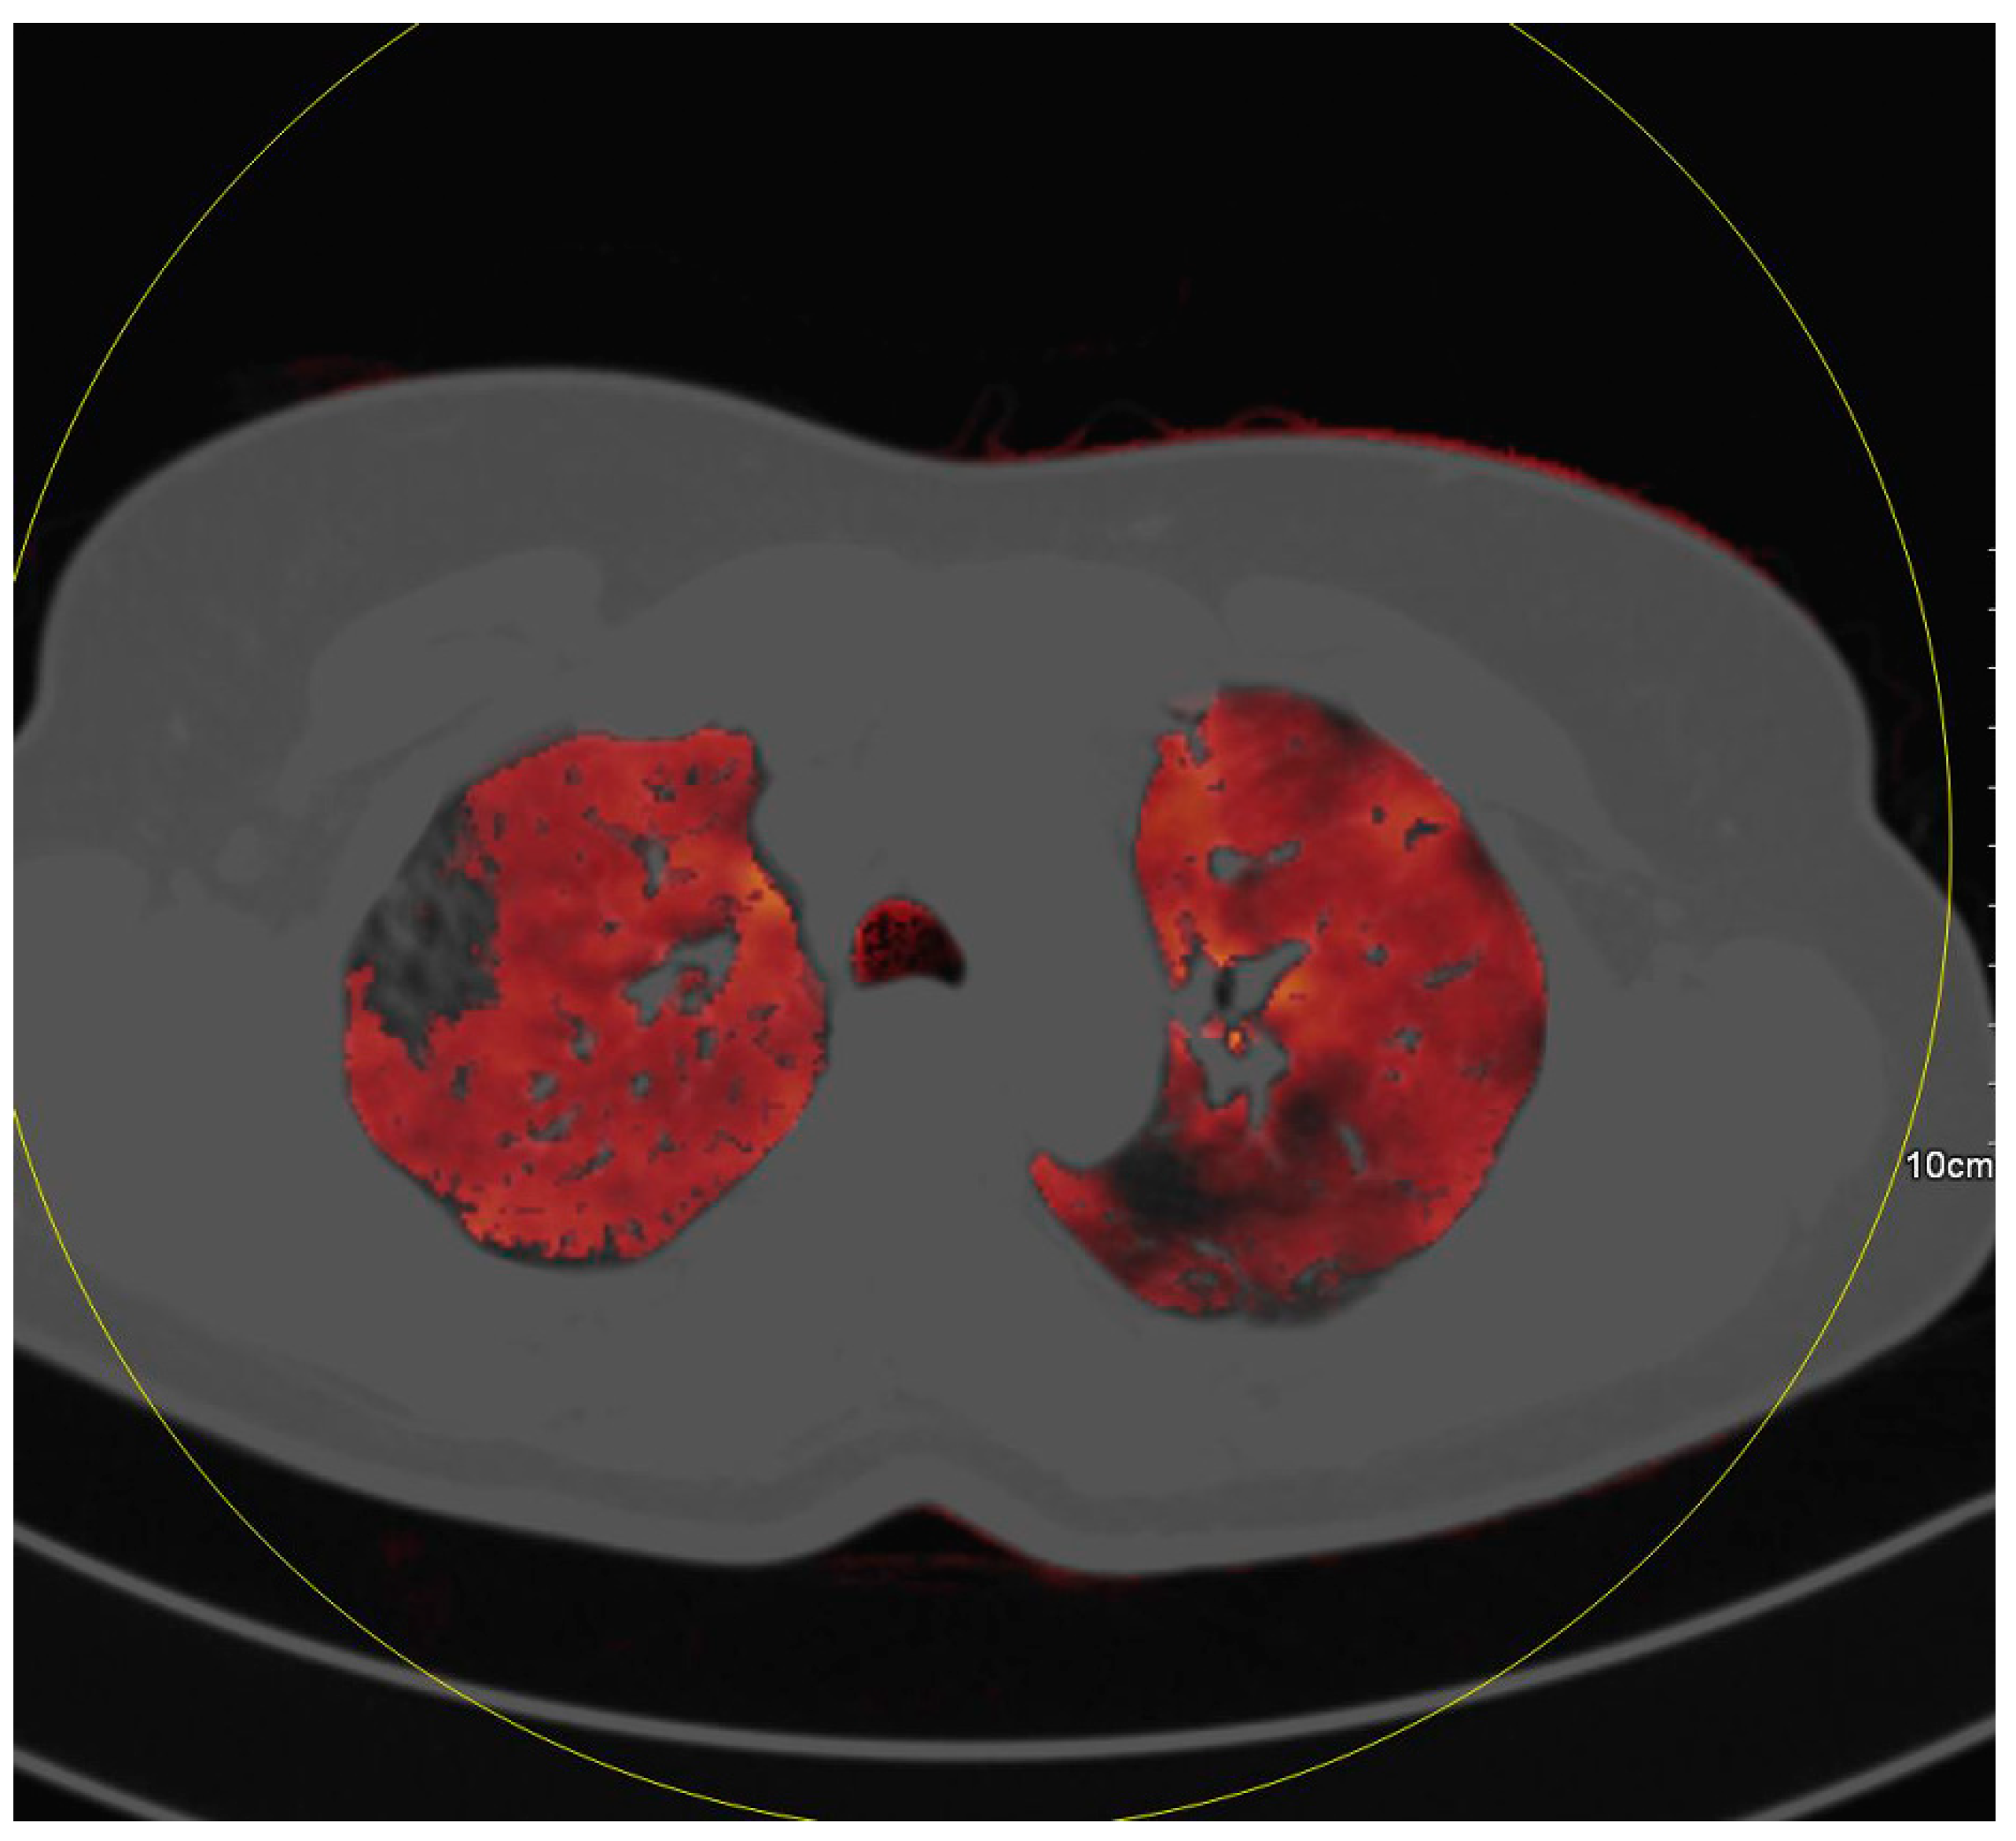

4. Discussion